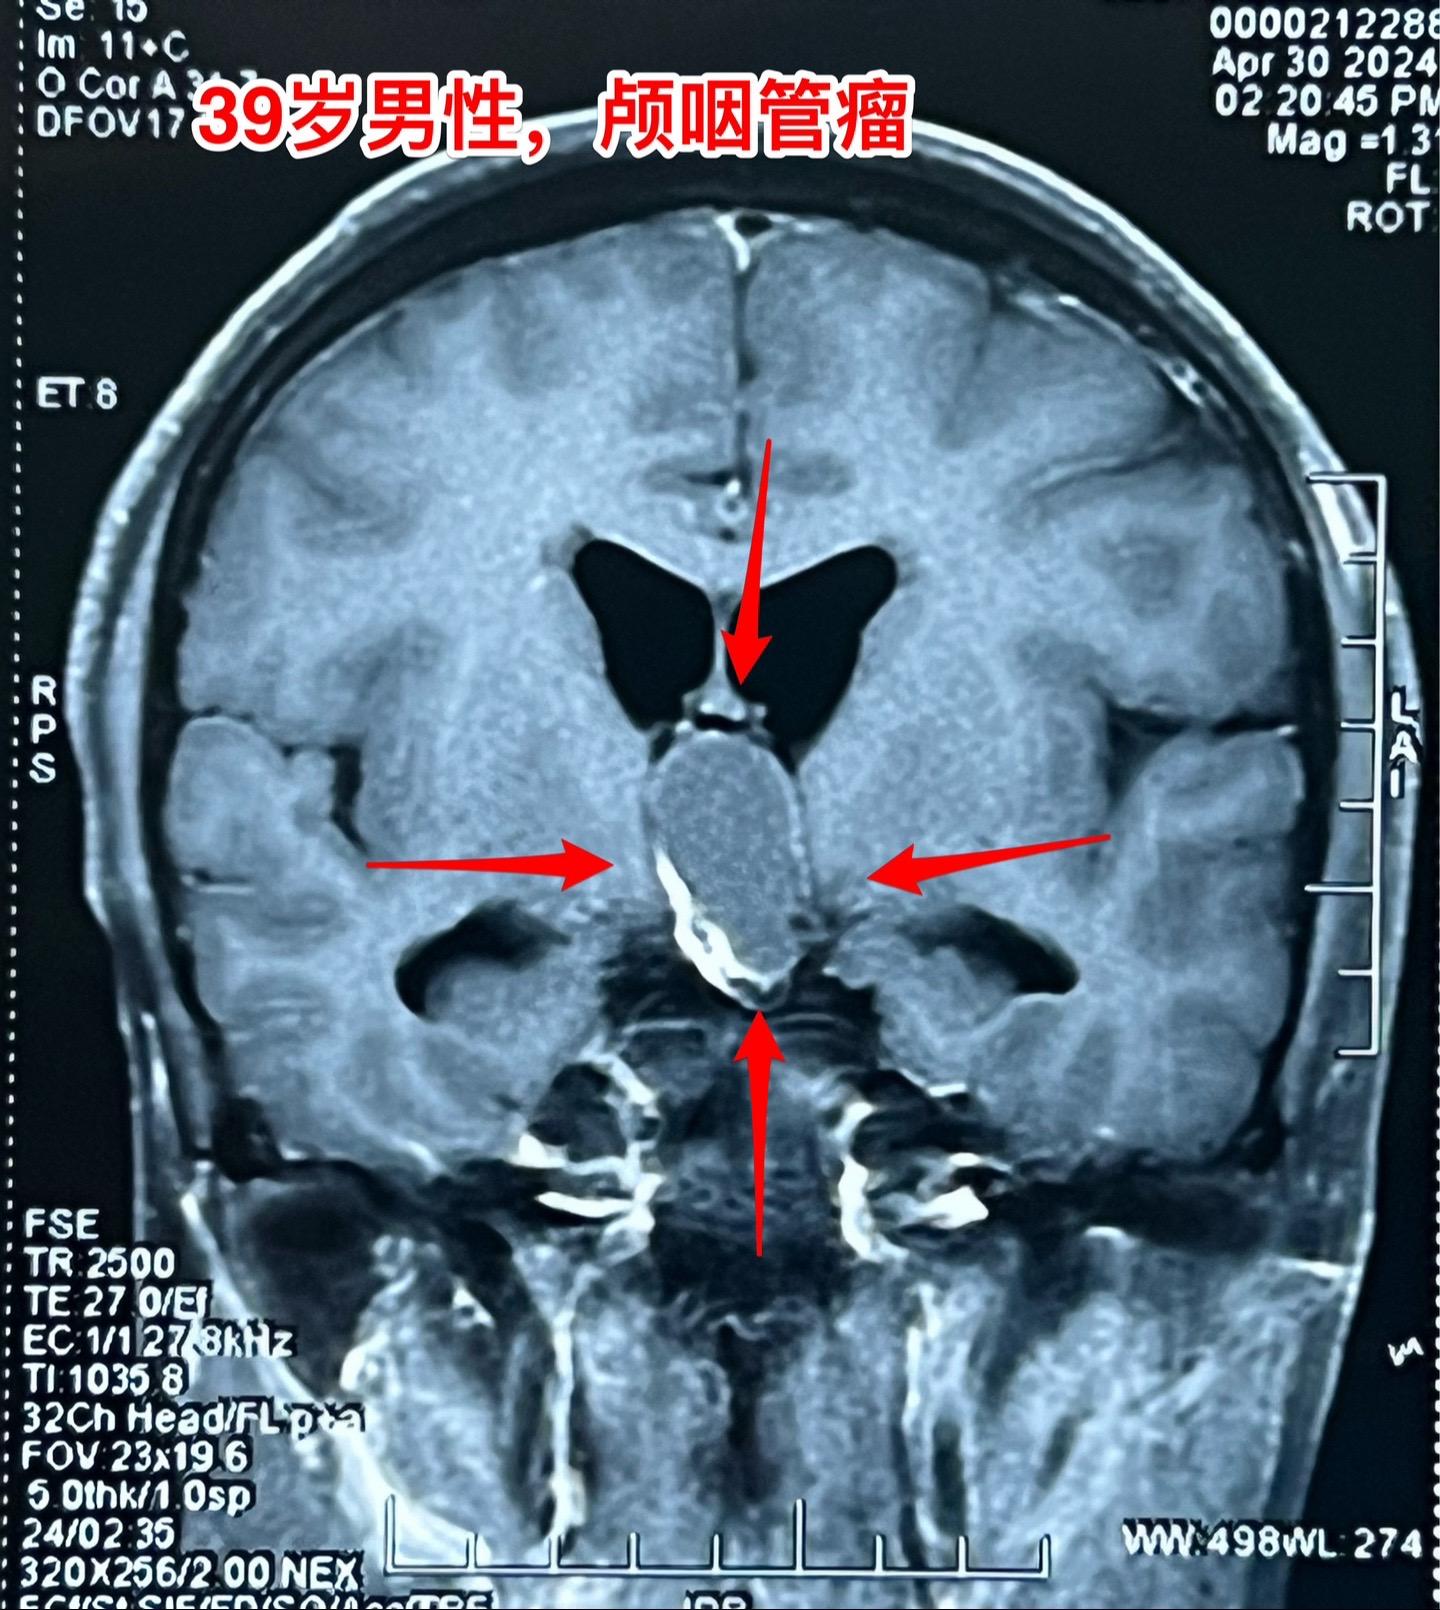

五月六日的颅咽管瘤手术。山西省男性,39岁,因为头痛、呕吐在4月29日就急匆匆的赶到三博脑科医院来住院。病因是颅咽管瘤造成颅压高,不能正常吃东西了。住院后用药物治疗,头痛症状减轻,也不呕吐,能正常进食。从图片可以看出这个颅咽管瘤属于细长型,从垂体窝延伸到第三脑室内,垂体窝里有大块钙化,手术是有难度的。 五一假期一过就排上手术,顺利切除肿瘤,手术后CT结果很让人满意,希望肿瘤不复发。